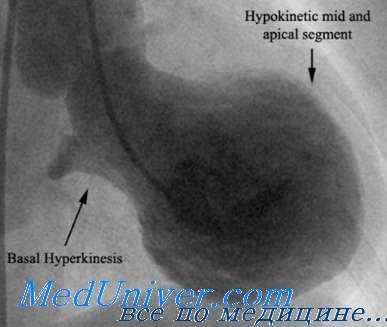

Как указывалось выше, характерные изменения регионарной сократимости включают гипо- или акинезию средних и верхушечных сегментов ЛЖ. При этом отмечается сохранение систолической функции базальных сегментов. Следует отметить, что нарушения сократимости миокарда обычно охватывают зону, превышающую ту, которая кровоснабжается какой-либо одной коронарной артерией.

Синдром такоцубо — транзиторное баллоноподобное расширение средней части верхушки сердца, сопровождающееся одновременной гиперкинезией базальных сегментов левого желудочка при отсутствии гемодинамически значимого стеноза венечных артерий (I51.81) [1].

Своим названием синдром обязан характерным изменением формы левого желудочка на эхокардиографии, возникающим за счёт акинезии/дискинезии и напоминающим японский глиняный сосуд — такоцубо, представляющий собой ловушку для осьминогов («тако» — осьминог, «цубо» — чаша). Ловушка-такоцубо — это 15-сантиметровый сосуд, который используется японскими рыбаками для ловли осьминогов на дне моря, в который они забираются как в жилище и оставляют снаружи только щупальца. Через некоторое время рыбаки вытаскивают ловушки за привязанную к ним верёвку вместе с осьминогами. Интересен тот факт, что приспособление такоцубо используется только рыбаками Хиросимы.